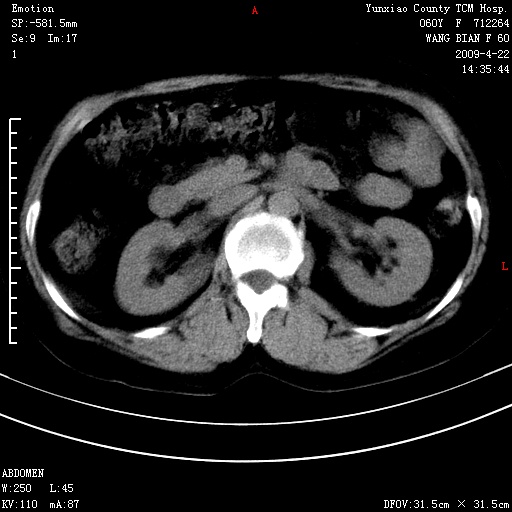

蛛网膜颗粒压迹 左肾低密度影囊肿可能。

不出外肾癌,强化下看

2、左肾囊肿。

脑正常,肾有事,须强化,再定性.

1、头颅未见明显异常。2、左肾囊肿可能。建议增强

1、枕骨蛛网膜粒压迹。2、左肾囊肿可能。建议增强

头颅未见明显异常。左肾囊肿。

1)枕骨蛛网膜粒压迹。2)左肾囊肿可能。

不出外肾癌,强化下看,枕骨蛛网膜粒压迹。

2、左肾囊肿可能性大。